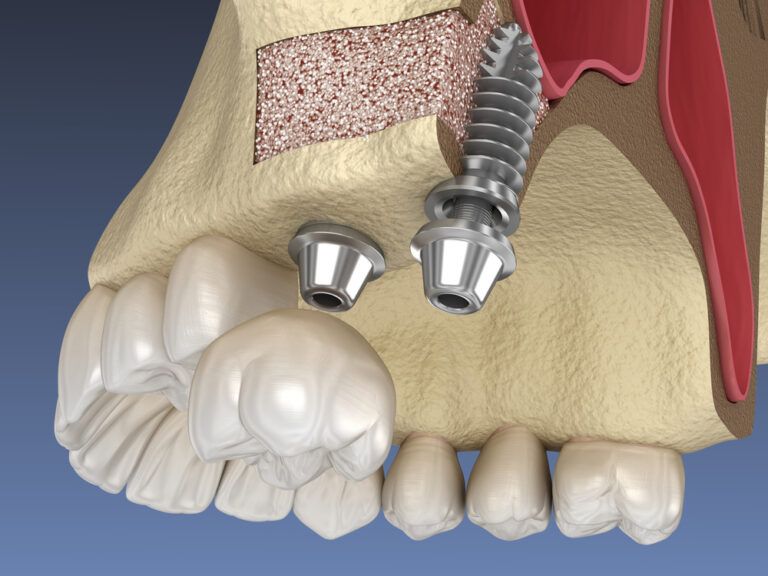

The Step-by-Step Process of Dental Implant Placement

Dental implants represent a groundbreaking advancement in restorative dentistry, offering a durable solution for replacing missing teeth and enhancing oral functionality. These artificial tooth roots, typically made from titanium, are surgically inserted into the jawbone, providing a strong foundation for

Endosteal Implants: The Standard in Implant Dentistry

Dental implants have revolutionized the way we approach the restoration of missing teeth, offering solutions that are not only functional but also aesthetically pleasing. Among the various types of dental implants available, endosteal implants stand out as the most commonly